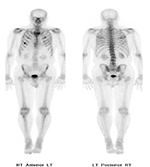

| PA Chest radiograph (A) demonstrates a sternal cage. Whole body Tc99m MDP images (B) demonstrate focal radiotracer activity in ribs bilaterally on the anterior view representing the sites of sternal cage fixation with bony reaction. |